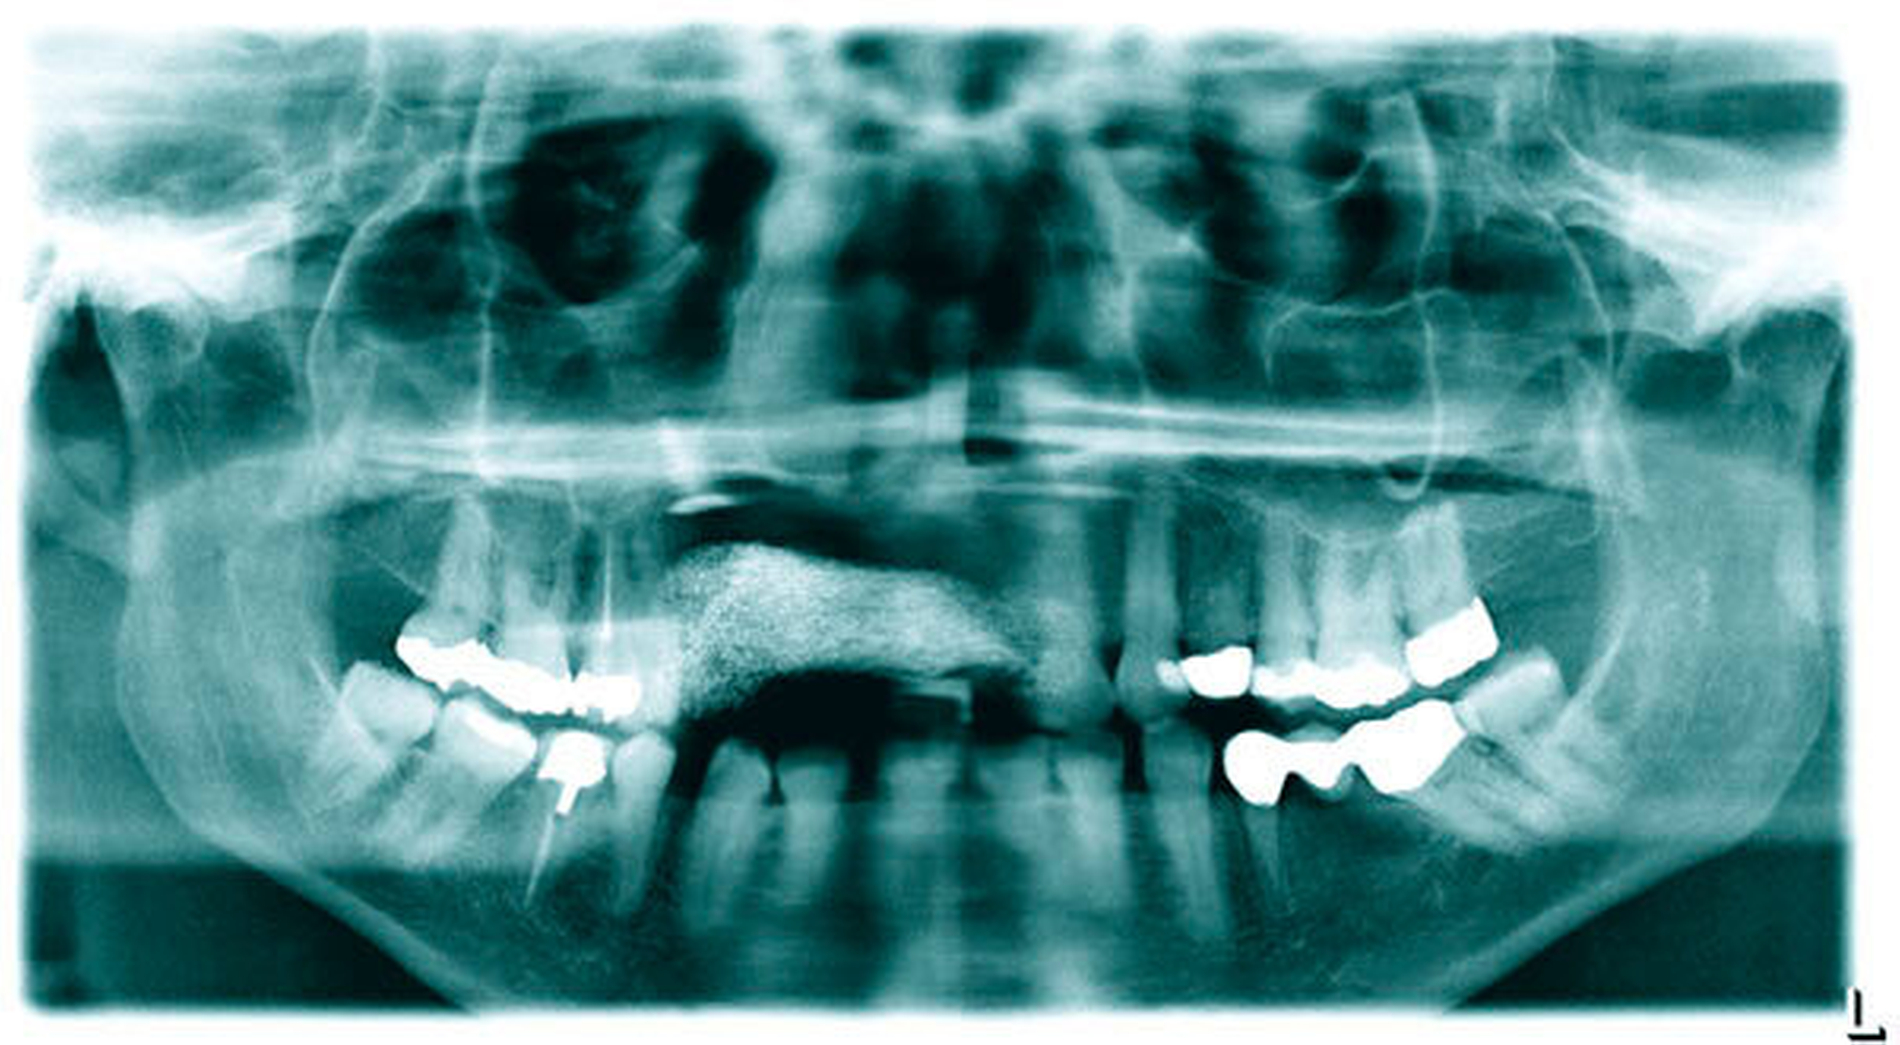

Zudem wurde eine postoperative Röntgenkontrolle mittels OPG durchgeführt (Abbildung 8). Bei optimaler Mundhygiene war der Heilungsverlauf Stadien-gerecht, ohne dass Dehiszensen oder eine Infektion aufgetreten wären.

In der Diagnostik kommt demnach neben der eingehenden oralen Inspektion der bildgebenden Untersuchung eine zentrale Bedeutung zu. Hierbei ist zu beachten, dass eine klassische konventionelle Panoramaschichtaufnahme als unzureichend gilt und – gerade auch im Sinne einer präoperativen Diagnostik – durch geeignete 3-D-Verfahren zu komplettieren ist. Außerdem wird empfohlen, eine histopathologische Aufarbeitung des Gewebes durchführen zu lassen, um zum einen maligne Prozesse ausschließen zu können und zum anderen die Diagnose zu sichern.

Eine OPG-Diagnostik ist bei Verdacht mit einer 3-D-Bildgebung zu komplettieren.